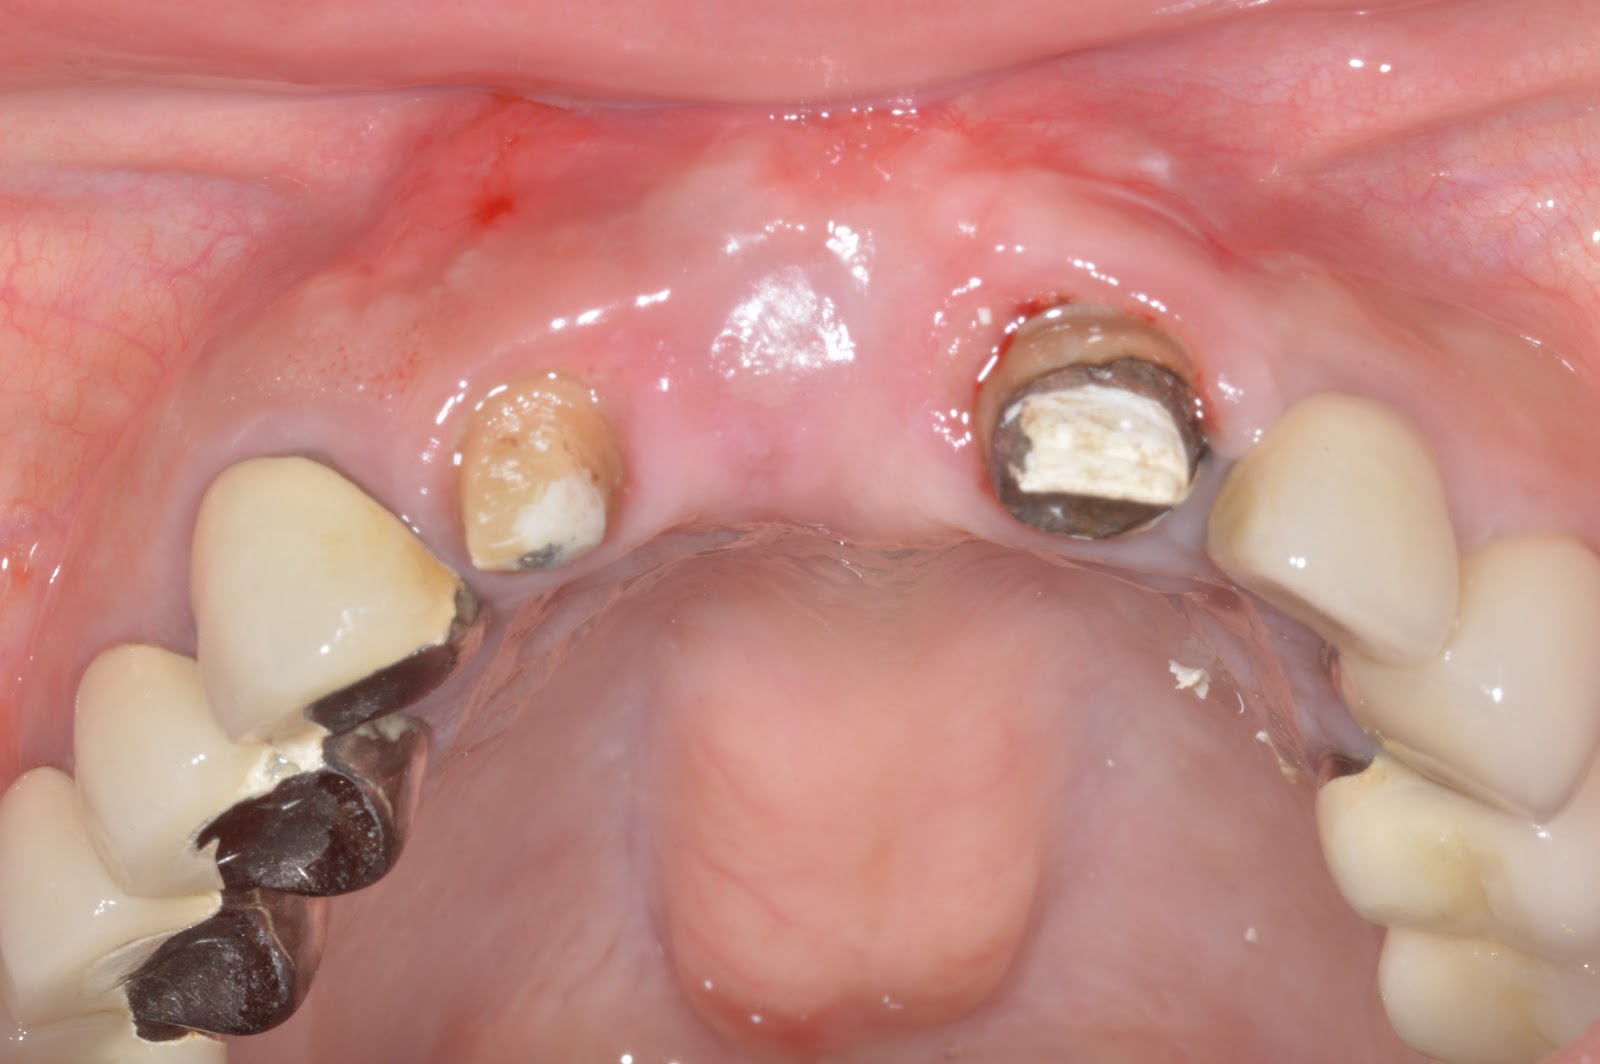

A severely ridge defect (H+V) after 3 times GBR/Soft tissue graft/Implant surgeries